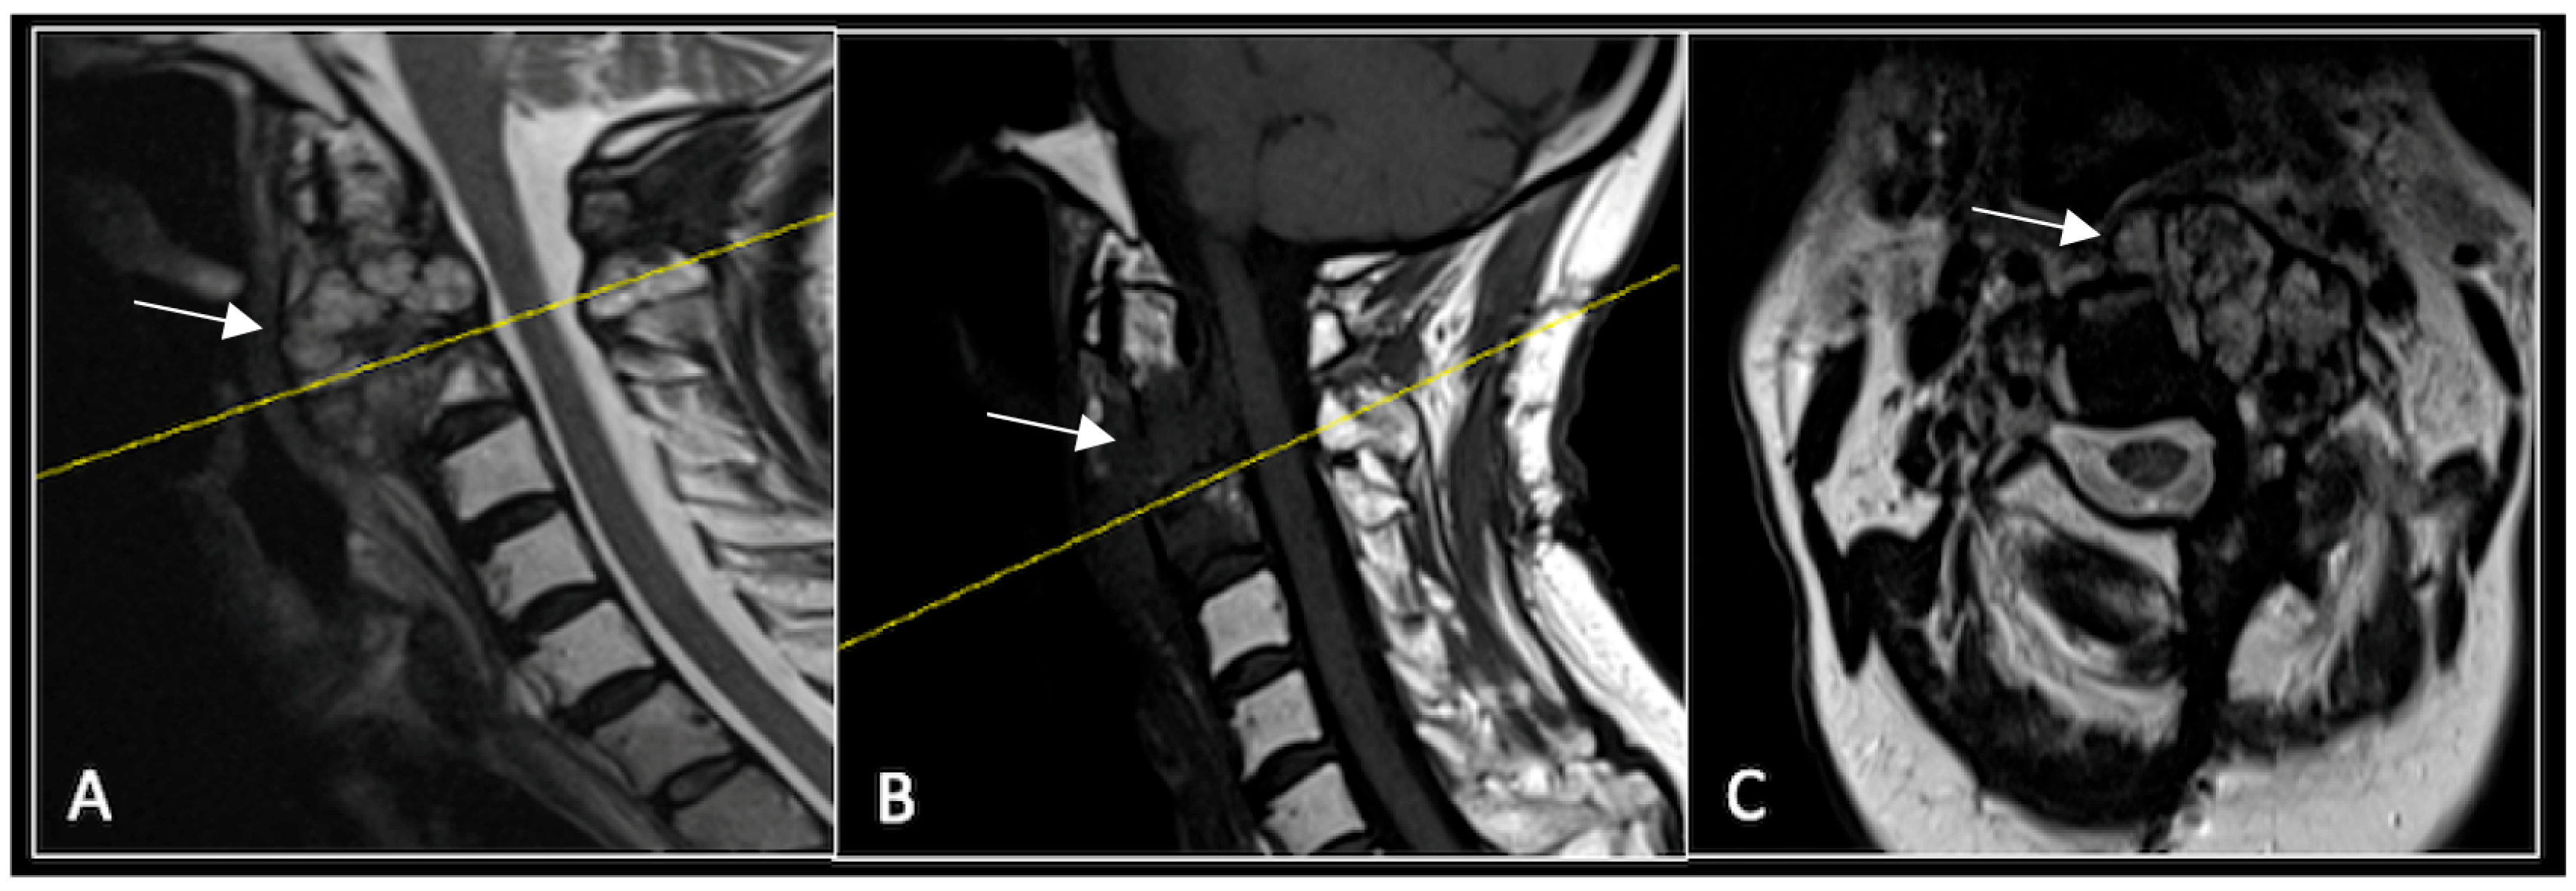

2.2. Case 2: Sacral Chordoma

This 63-year-old male presented with sacral pain and right-sided S1 radiculopathy. He was subsequently referred to our institution after diagnostic imaging revealed a destructive lesion within the S1 vertebra (Figure 4). The patient developed symptoms of acute cauda equina syndrome, for which we recommended an emergent surgical decompression to be performed at the referring hospital. Biopsy confirmed a conventional chordoma. The patient chose to undergo separation surgery, given the significant morbidity associated with an en-bloc sacral resection, including sacrifice of the neural structures innervating his bladder and bowel. He received adjuvant proton beam therapy, and 6-monthly surveillance imaging revealed stable disease (Figure 5). Unfortunately, 12 months post-separation surgery, there was evidence of tumour progression with epidural extension and symptomatic deterioration in bladder function, requiring revision surgical debulking (Figure 6).

Figure 4.

MRI demonstrating a destructive lobular sacral mass (arrow) with invasion of the S1 vertebral body and complete compression of the cauda equina neural elements. The yellow line on the axial image represents the plane of the corresponding axial section. (A) T2W sagittal; (B) T1W sagittal; (C) T2W axial.